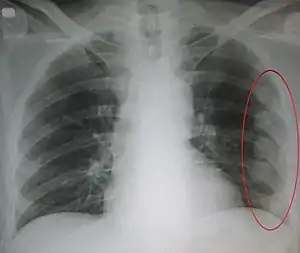

- Pleural effusion[1]

- Pleural effusion[4]